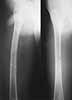

This patient,a middle aged malewas a diagnosed case of hypophosphatemic osteomalacia on treatment. Unfortunately he discontinued treatment since he was poor and also neutral phosphate was not available locally. He presented with pathological fracture of left femur and a failing neck of same femur.

We managed to get neutral phosphate, initiated medical treatment and did an antegrade SIGN nailing of left femur along with couple of screws to neck using miss a nail technique. He complained of pain of the right femur and both forearms. In OT these areas were screened using image intensifier and found that he has looser zones of all these with impending fractures. Yesterday we did a retrograde nailing of right femur usingSIGN nail. Both ulnas were stabilised usingLambrudini wires in a closed fashion. All fractures and looser zones were stabilised by closed surgery using image intensifier. It may be interesting to see the post of picture of both the hips in which one side shows an antegrade femoral SIGN nail and the other side shows a retrograde SIGN nail.